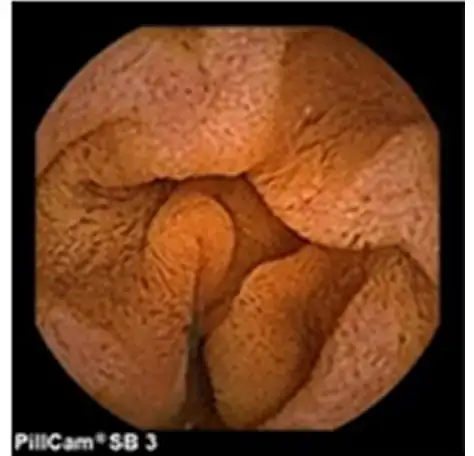

カプセル内視鏡検査

主に小腸を調べる検査です。

小腸ダブルバルーン内視鏡検査

尺取虫の様な機能の内視鏡で、小腸を調べる検査です。